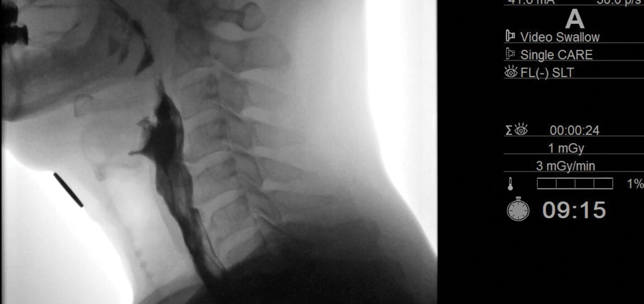

Laryngology / Swallowing / Voice

Taking life by the throat